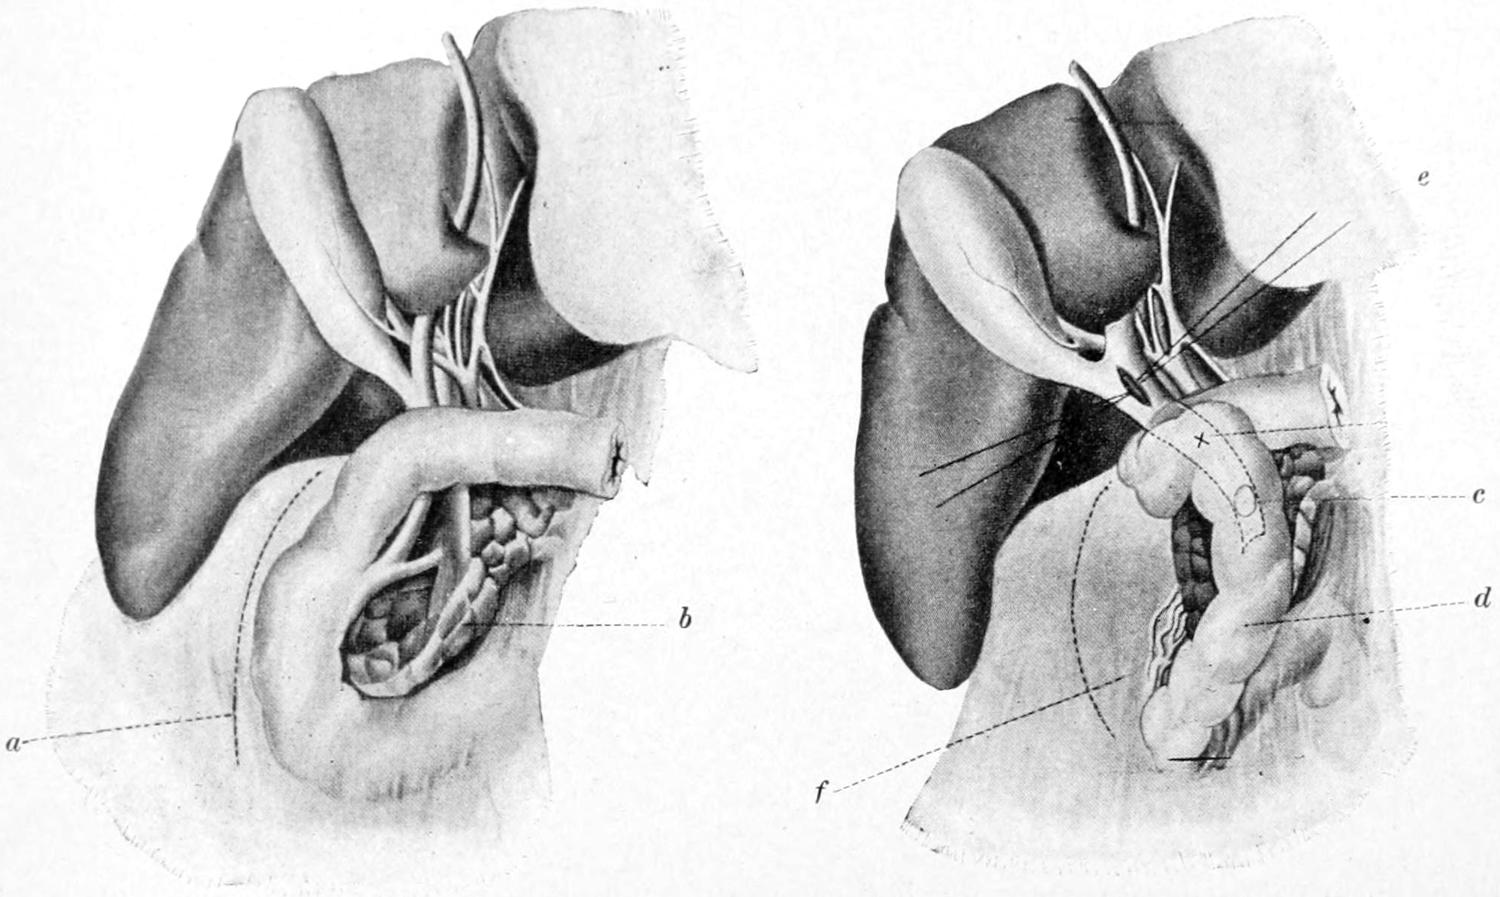

THE OMENTUM, THE MESENTERY, THE SPLEEN AND THE PANCREAS 934